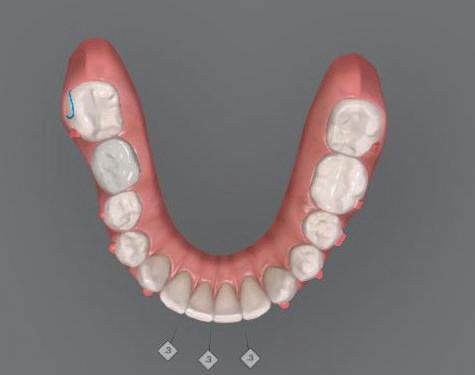

След диагностиката бяха направени екстра- и интраорални снимки, както и рентгенографии; професионалното почистване бе от изключителна важ ност, бяха дадени и инструкции за лич на орална хигиена. Бе направено интра орално сканиране с Medit i500. Цялата тази информация бе използ вана в приложението Smilecloud за 2D биометричен дизайн. В приложението са налични естест вени форми на зъбите и щом бяха под брани зъби и бе направен дизайн

библиотеката на Exocad. Струва си да се отбележи, че 2D дизайнът от Smile Cloud бе спазен до последния детайл в Exocad smile creator с цел да се създаде 3D obj файл със зъбните форми. След като естетичният дизайн бе готов в model creator модула на Exocad, адитивен 3D мок-ъп модел бе експорти ран и принтиран от принтер Formlabs 3. Моделът бе използван за направата на силиконов водач, за да се изготви мо тивационен мок-ъп в устата на паци ента и да се оценят естетичните па раметри. След като пациентът одобри вида на усмивката си, мок-ъпът бе използван за финализиране дизайна на усмивка та. Мок-ъпът бе използван също така като водач по време на мекотъканна та хирургия, както и при препарация на зъбите.

Препарираните зъби бяха импорти рани в Exocad и насложени върху ес тествените форми от биометричния дизайн, като така стана ясно дали зъ бите са били препарирани коректно. По този начин зъболекарят и зъботехни кът работят в една и съща екосистема и резултатът е оптимален. С короната се справихме чрез диги тална редукция на циркония в Exocad, като по този начин на практика създа дохме циркониево кепе, след което про изведохме фасета от IPS Empress Cad Multi. Кепето от Katana Zirconia на зъб 12 с букално послойно нанесена керами ка бе фрезовано (послойното нанасяне бе направено, за да се подобри връзката и да се осигури адхезивно циментиране на фасетата към циркониевото кепе, както и за да се напасне цветът към този на съседните зъби). При първото сканиране регистрирах ме цялата горна зъбна дъга, така че, ко гато се наложи да сканираме повторно, бе изтрит и сканиран наново само зъб 12, тъй като венците не бяха отдръп нати при второто сканиране.

рентгенографии. Инициална терапия и професионално почистване. Интраорално сканиране с цел диги тално планиране. Регистрация и 3D ориентиране на ок лузалната равнина на горна и долна челюст в пространството. 2D дигитално планиране и дизайн на усмивката посредством приложение то Smile Cloud. 3D дигитално планиране и дизайн на функционалните и естетичните па раметри. 3D дигитален дизайн и адитивен мокъп на горна челюст. 3D принтиране и мок-ъп модели. Мотивационен мок-ъп. Фини корекции за постигане на фи налния дизайн. Мекотъканна хирургия с мок-ъпа като водач Препарация през мок-ъпа, използвай ки дизайна като водач за финалната препарация в Exocad. Циркониево кепе ще бъде циментира но с цел адхезивно залепяне на фасе та на края. Кепето има същия цвят като този на съседните зъби, за да може фасетата да се впише перфект но в цялостната усмивка. Изработване на 12 IPS Empress Cad Multi фасети с послойно нанесена ке ТОТАЛНА РЕХАБИЛИТАЦИЯ НА УСМИВКАТА С ИЗЦЯЛО ДИГИТАЛЕН ПРОТОКОЛ Д-р Калин Маринов и зт. Стефан Петров рамика букално върху зъбните препа рации и върху първичното циркони ево кепе (има възможност за ецване и адхезивно